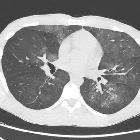

CT

The HRCT pattern can vary with time of onset of the hemorrhage and the clinical context is crucial in image interpretation:

- acute phase

- can range from lobular or lobar areas of ground-glass opacities to predominant consolidation

- ground-glass opacity is generated by subtotal alveolar filling with blood and is accompanied by the apparent prominence of segmental and subsegmental bronchi, which has been referred to as the “dark bronchus sign"